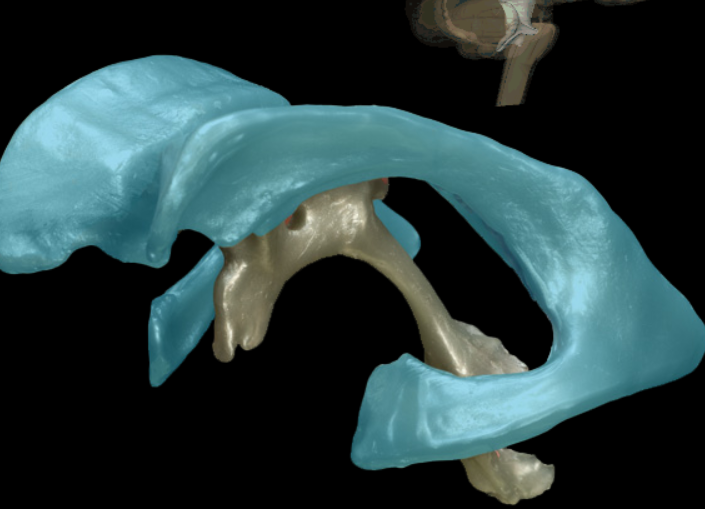

falx cerebri

falx cerebelli

tentorium cerebelli